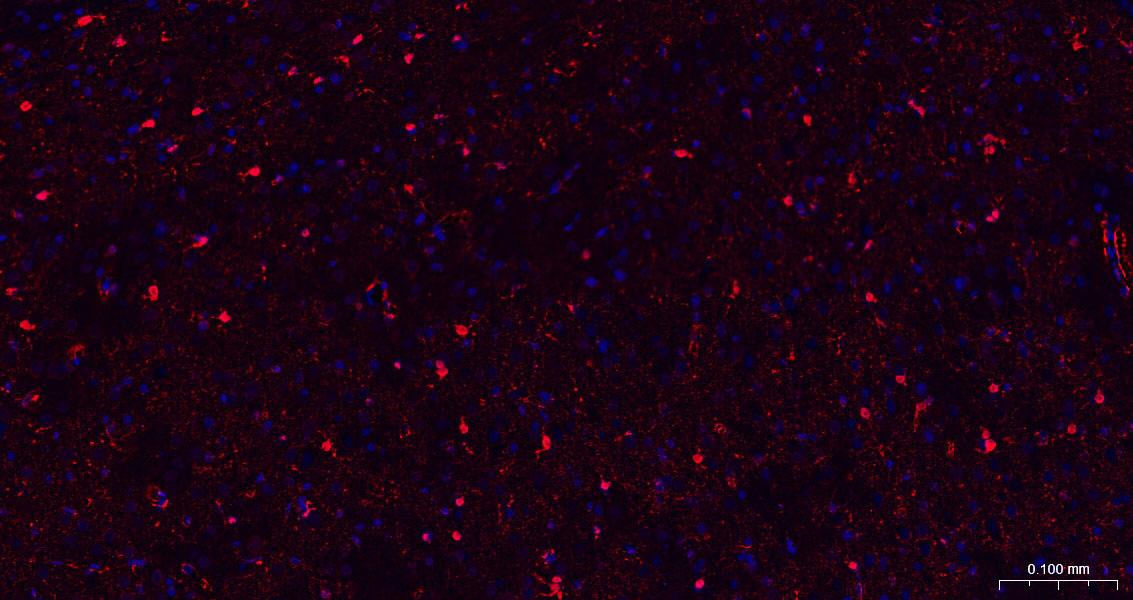

Paraformaldehyde-fixed, paraffin embedded Rat Cerebrum; Antigen retrieval by boiling in sodium citrate buffer (pH6.0) for 15 min; The section was incubated with S100B Monoclonal Antibody, Unconjugated (bsm-52506R) at 1:200 overnight at 4°C. Followed by conjugated Goat Anti-Rabbit IgG antibody (Red, bs-0295G-BF594), DAPI (blue, C02-04002) was used to stain the cell nuclei.